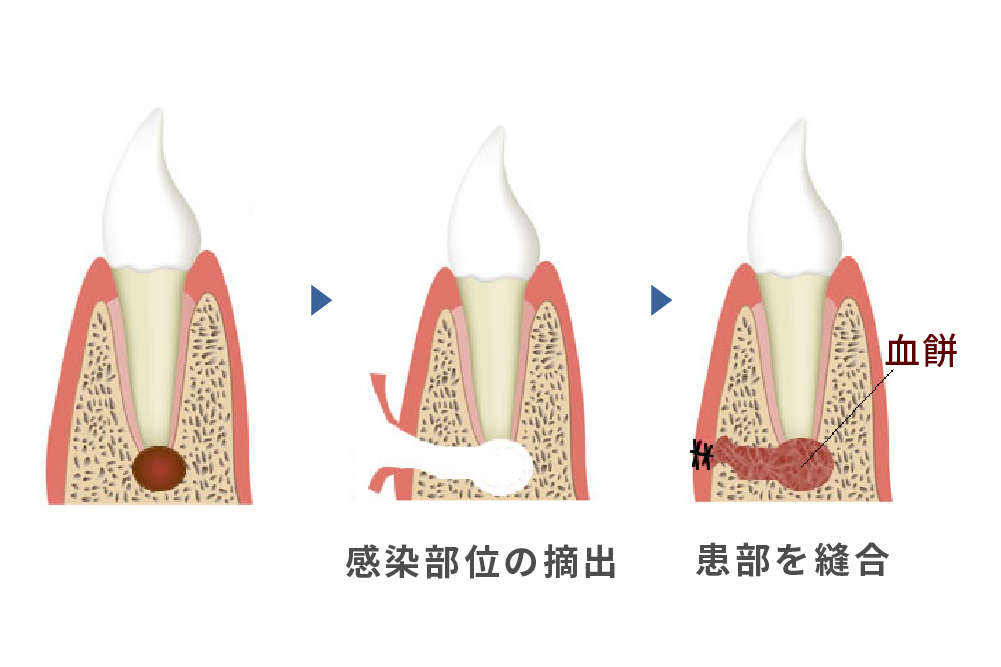

(根尖切除術・意図的再植術)